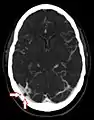

КТ ангіографія показує павутинні грануляції в лівому поперечному синусі